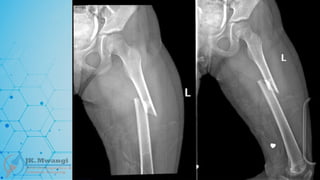

CLASSIFICATION

• Bone = 3

• Segment = 3

• Type = C

• Group = 3

• 33-c3

• Segment = 2

• Type = A

• 32-A3